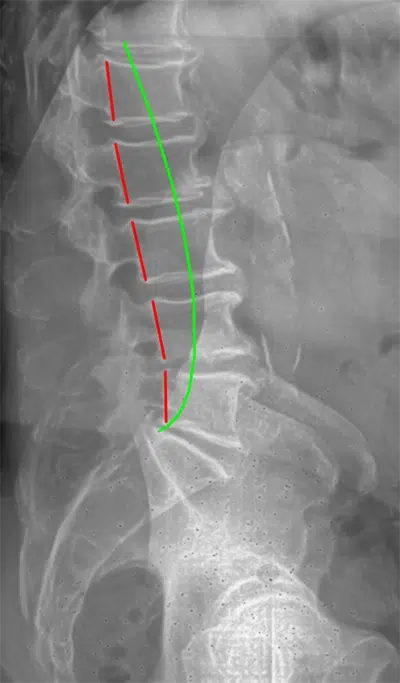

• Precision Digital X-rays: If necessary, we take high-resolution images to see the exact alignment of your spine, allowing us to create a blueprint for your recovery.

• Chiropractic BioPhysics® (CBP): We don't "crack" your back. We use the most researched chiropractic technique in the world to physically reshape your spinal curves toward their ideal, healthy alignment.

Chiropractor Traverse City MI X Ray